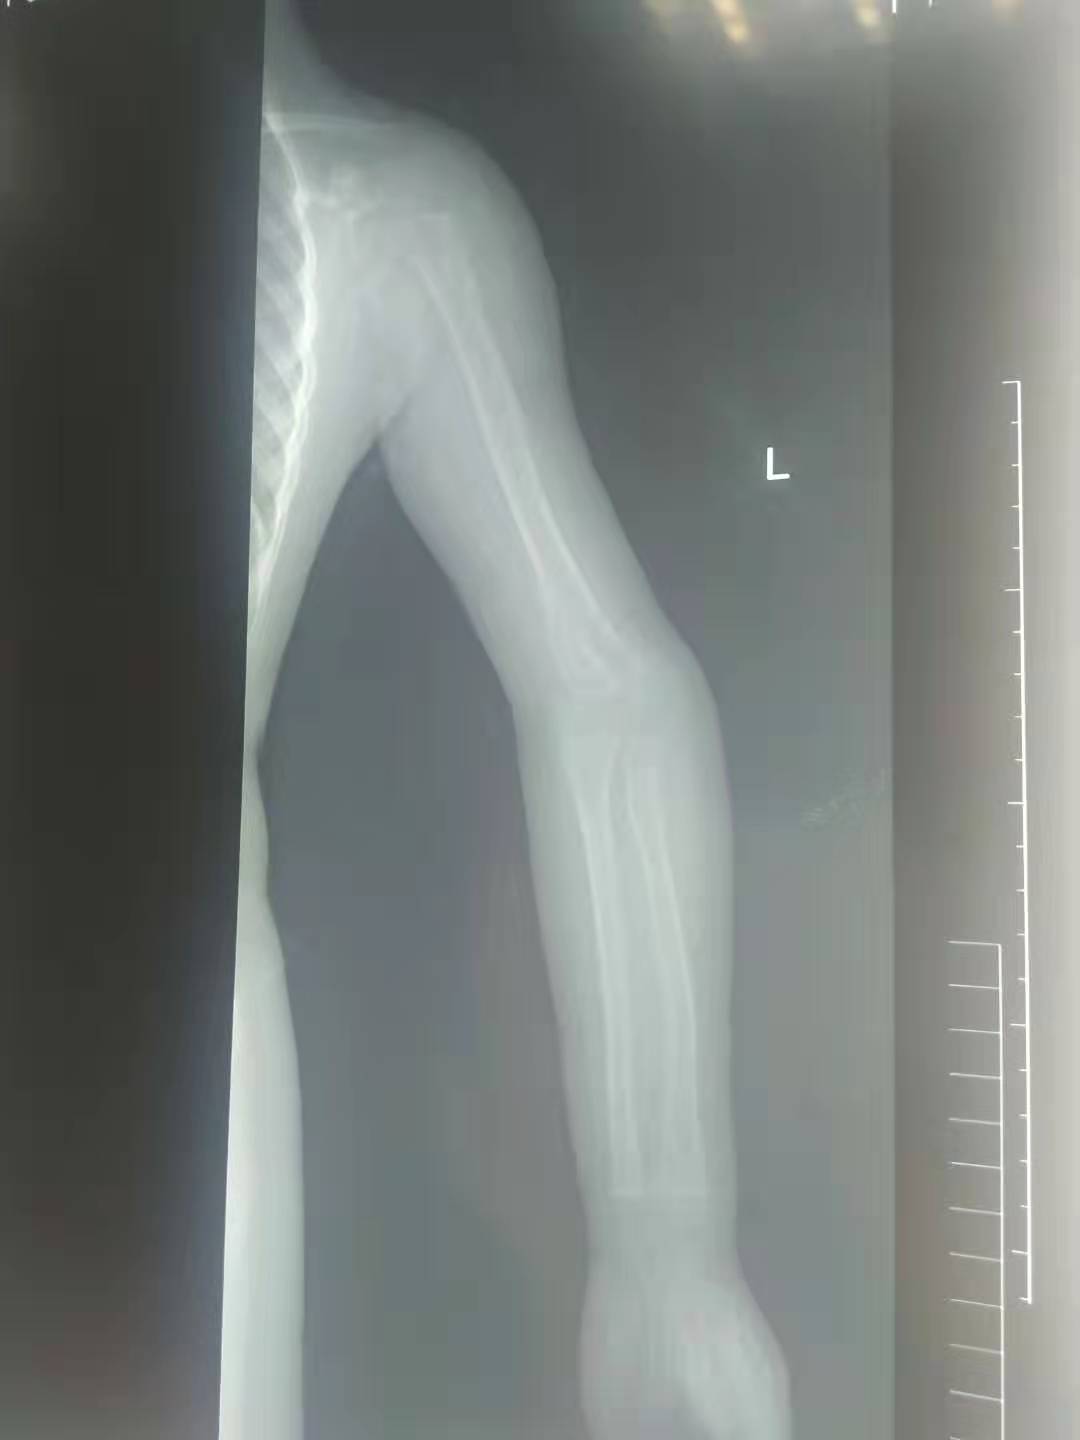

五岁的小女孩,因为小时候的意外导致了手肘骨折,当时不过一岁半的小女孩,没有及时告诉自己的妈妈,小女孩的妈妈发现了异常,小女孩手抬不起来,这可把这位妈妈给急坏了,立即带着孩子赶去了当地的医院,经过检查发现小女孩的手肘骨折错位,当时由于孩子太小,所以没有做手术,于是给予了手法复位,打了石膏,夹板;时隔两年,孩子的妈妈发现,孩子手肘与正常的手肘有些不一样,因为孩子太小,医生提议在孩子在大点的时候给予手术修型纠正。孩子的手有些畸形,没有出现什么功能障碍,只是对于一个孩子来说,影响外形。

骨折的手